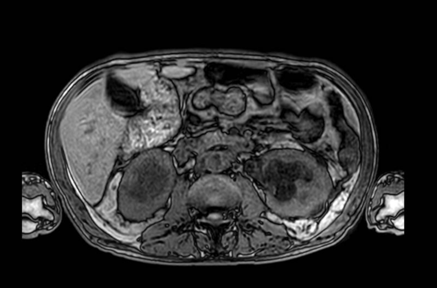

Figure 1. Abdominal Magnetic Resonance Imaging: Irregular solid mass located in the retroperitoneum, measuring approximately 8.7 × 2.8 × 5.8 cm, involving vascular structures such as the abdominal aorta and inferior vena cava. The lesion causes marked bilateral hydronephrosis. Bilateral renal cysts (Bosniak 1 and 2), diffuse thickening of the bladder wall, and an enlarged prostate are also observed. Findings are compatible with a retroperitoneal expansive/infiltrative process.